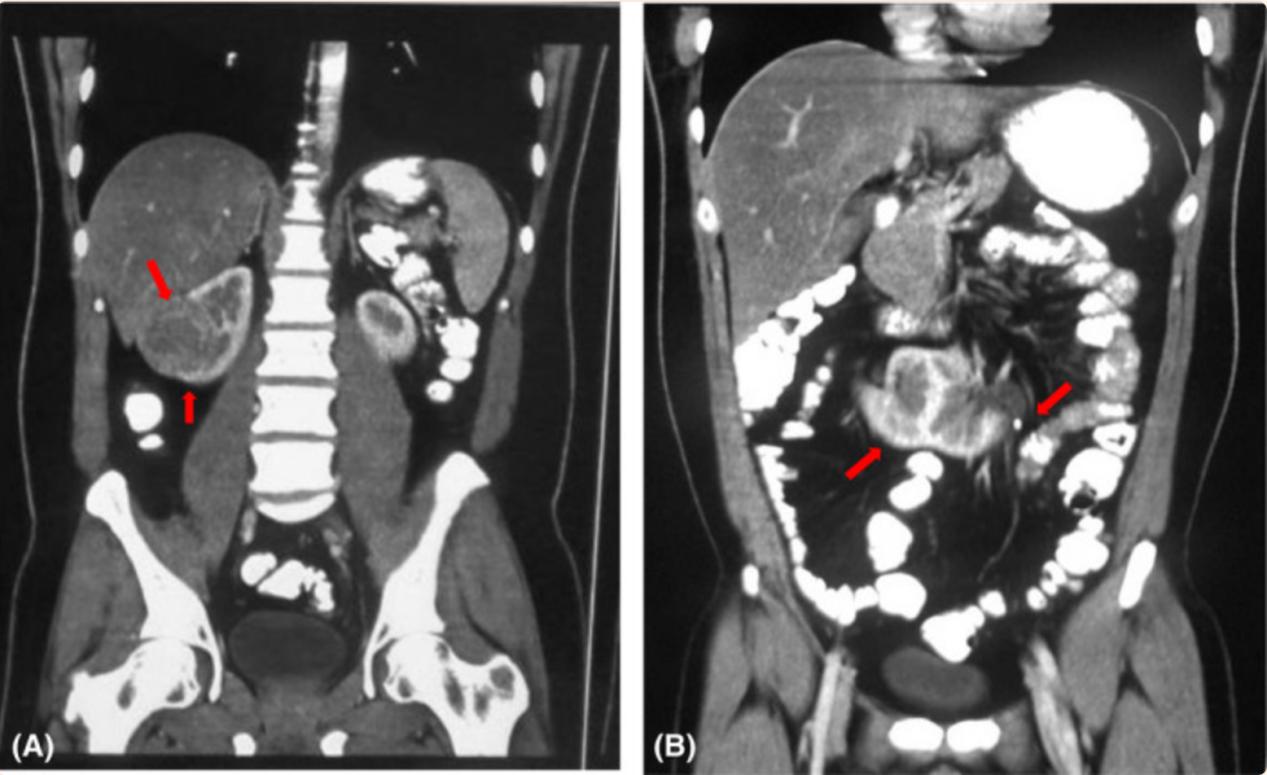

肾脏超声检查结果显示一个清晰的圆形异回声固体肿物(52 × 51 mm),在右肾中极向肾外延伸 (103mm),压迫肾窦。左肾旋转不良,位于正常解剖部位的尾部(图1)。随后,腹部和骨盆螺旋计算机断层扫描(CT)和腹部磁共振成像(MRI)显示 右肾中极50× 53 × 48 mm肿物,影响邻近右肝叶的肾盂输尿管系统,提示肾细胞癌(RCC),以及左输尿管近端一4mm结石,距离HK左侧肾盂输尿管连接处21mm(图2和3)。肾结石类型为草酸钙。在此之前,患者没有意识到自己的肾脏异常,也没有观察到任何泌尿系统相关症状。

图3 腹部和骨盆螺旋CT扫描(A) 右肾中极50× 53 × 48 mm肿物,影响邻近右肝叶的肾盂输尿管系统(B) 左输尿管近端一4mm结石,距离HK左侧肾盂输尿管连接处21mm